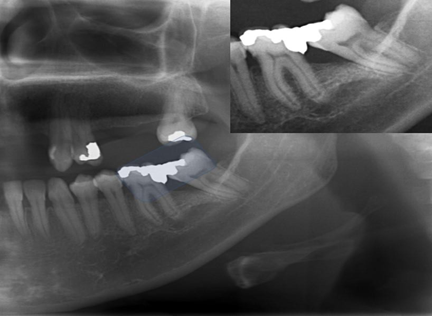

In the study by Brunsvold & Lane,5 33% of adult patients had excess restorations and they found that these restorations are related to the progression of periodontal disease, as in addition to promoting the accumulation of biofilm, they contribute to an alteration in the subgingival microbiota. Waerhaug reports that alveolar bone loss in regions with excess restorations is more associated with biofilm accumulation, with a percentage of 32% of proximal excess in the cases analyzed by him and his team, which was corroborated by the study by,25 who found the presence of 40.69% of teeth restored with proximal excess Figure 3–12.

Figure 5 Periapical radiography of the molars and lower premolars region D. The dotted oval areas identify endodontic treatments for tooth roots 46. There is a prosthetic fused metal core to support the metallic crown on that same tooth. See that the root fillings are below the apical limit, and this characterizes iatrogeny. There is an apical radiolucent image, which may mean repair.

Figure 7 Panoramic X-ray cutout showing highlighted tooth 36, mesiangulated, with a coarse excess on its distal face, that causes iatrogeny, even though it has free access due to the absence of tooth 37. This tooth was treated endodontically, at first, in a correct way.

Figure 8 Panoramic X-ray cutout showing highlighted teeth 36 and 38, with a coarse excess on its distal face of tooth 36. In fact, there is an entire contact face, instead of a contact point, too, due to mesiangulation of tooth 38 that causes iatrogeny .

Figure 9 Panoramic X-ray cutout showing highlighted tooth 48, with some mesiangulation. Note that in iatrogenic endodontic treatment of the mesial root, one of the root canals is partially filled. This may be causing the space in the apical periodontal ligament to increase in that root .

Figure 10 Panoramic X-ray cutout showing highlighted tooth 46, with correct endodontic treatment and with a coarse excess on its mesial surface, that causes iatrogeny. As the tooth is dead, the patient will be slow to feel the symptoms of this iatrogeny, excess restoration, which will possibly destroy the tooth. Note that there is already a caries infiltration.

Figure 11 Panoramic X-ray cutout showing highlighted tooth 46, with iatrogenic endodontic treatment. There is a prosthetic crown with a fused metallic core with a larger support at the distal root. Note that in endodontic treatment there is a lack of material in both roots, and apical radiolucent images of these, partially diffuse, greater in the mesial root, compatible with apical lesion such as chronic abscess or granuloma. Both have a slow characteristic, due to the halo, or condensing osteitis that has formed around the lesions. Tooth 45 also has an endodontic treatment, but it is correct.

Figure 12 Periapical radiographic images of the premolars and left molars, where we point with the red arrows, the resorption of the alveolar bone crest between teeth 25-26, due to the lack of contact point between these teeth, exacerbated by the lack of contour of the teeth. restorations in the respective proximal boxes. This iatrogenesis is causing the periodontal problem.

In addition to instrument fractures, anatomical deformations of the canal can occur, such as the formation of steps and root perforations,26 our data show that 26.27% of the analyzed patients have some failure of the endodontic treatment. Thus, some factors can be raised in order to explain the data found in this work.21-23,27–29,32